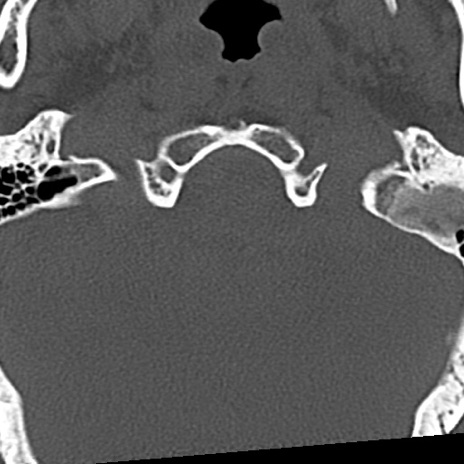

頚椎CT

横断像